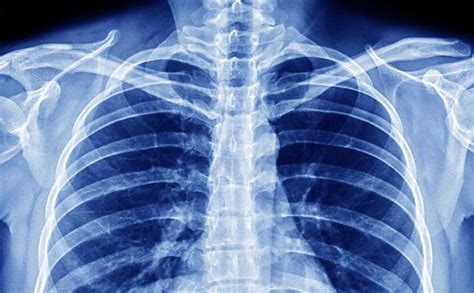

La diagnosi precoce e accurata è essenziale. La valutazione iniziale in pazienti con sintomi respiratori o febbre comprende la radiografia del torace e la valutazione dell'ossigenazione, solitamente tramite pulsossimetria.

Se la radiografia del torace mostra un infiltrato o se è presente ipossiemia, sono necessari ulteriori accertamenti. Una radiografia del torace può essere normale nella polmonite da Pneumocystis jirovecii, ma spesso si associa a ipossia o a un aumentato gradiente alveolo-arterioso di ossigeno.

Nei casi in cui il sospetto clinico di polmonite è elevato ma la radiografia del torace non è conclusiva, una TC del torace è raccomandata. Vengono eseguiti test sull'espettorato e emocolture.

Interpretazione delle Immagini Radiologiche

Le caratteristiche radiologiche possono fornire indizi sull'eziologia:

- Consolidamento localizzato: Suggerisce infezioni batteriche (incluso Nocardia), micobatteri o funghi.

- Quadro interstiziale diffuso: Più indicativo di infezioni virali, polmonite da P. jirovecii, danno da farmaci o radiazioni, o edema polmonare.

- Lesioni nodulari diffuse: Possono indicare micobatteri, Nocardia spp., funghi o tumori.

- Malattia cavitaria: Suggerisce infezioni da micobatteri, Nocardia spp., funghi o batteri, in particolare S. aureus.

- Polmonite interstiziale bilaterale in riceventi di trapianto: Eziologie comuni includono il citomegalovirus o cause idiopatiche.

- Consolidamento a base pleurica: Solitamente associato a infezioni da Aspergillus.

- Polmonite bilaterale in pazienti con AIDS: Spesso è polmonite da P. jirovecii.